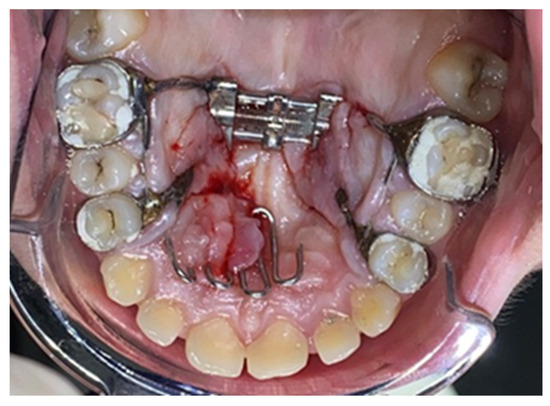

A Retrospective Histological Study on Palatal and Gingival Mucosa Changes during a Rapid Palatal Expansion Procedure

2.2. Palatal Expander Placement

2.3. Assessment of the Study Group